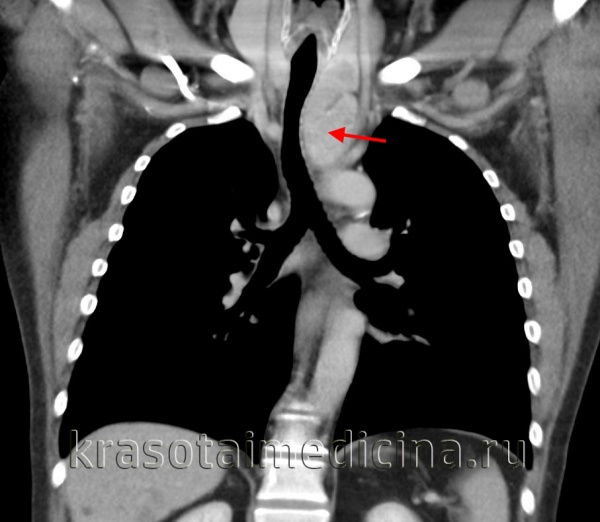

Лимфомы медиастинальной локализации не всегда диагностируются при рентгенологическом обследовании. Компьютерная томография, более детально, чем обзорная рентгенография позволяет рассмотреть конгломерат опухоли, увеличение лимфоузлов средостения, вовлечение паратрахеальных, трахеобронхиальных, прикорневых лимфатических узлов. Диагностическая значимость магнитно-резонансной томографии в верификации лимфом средостения признается не всеми авторами.

КТ ОГК. Объемное образование в средостении (патологически измененный лимфоузел), подтвержденная лимфома.